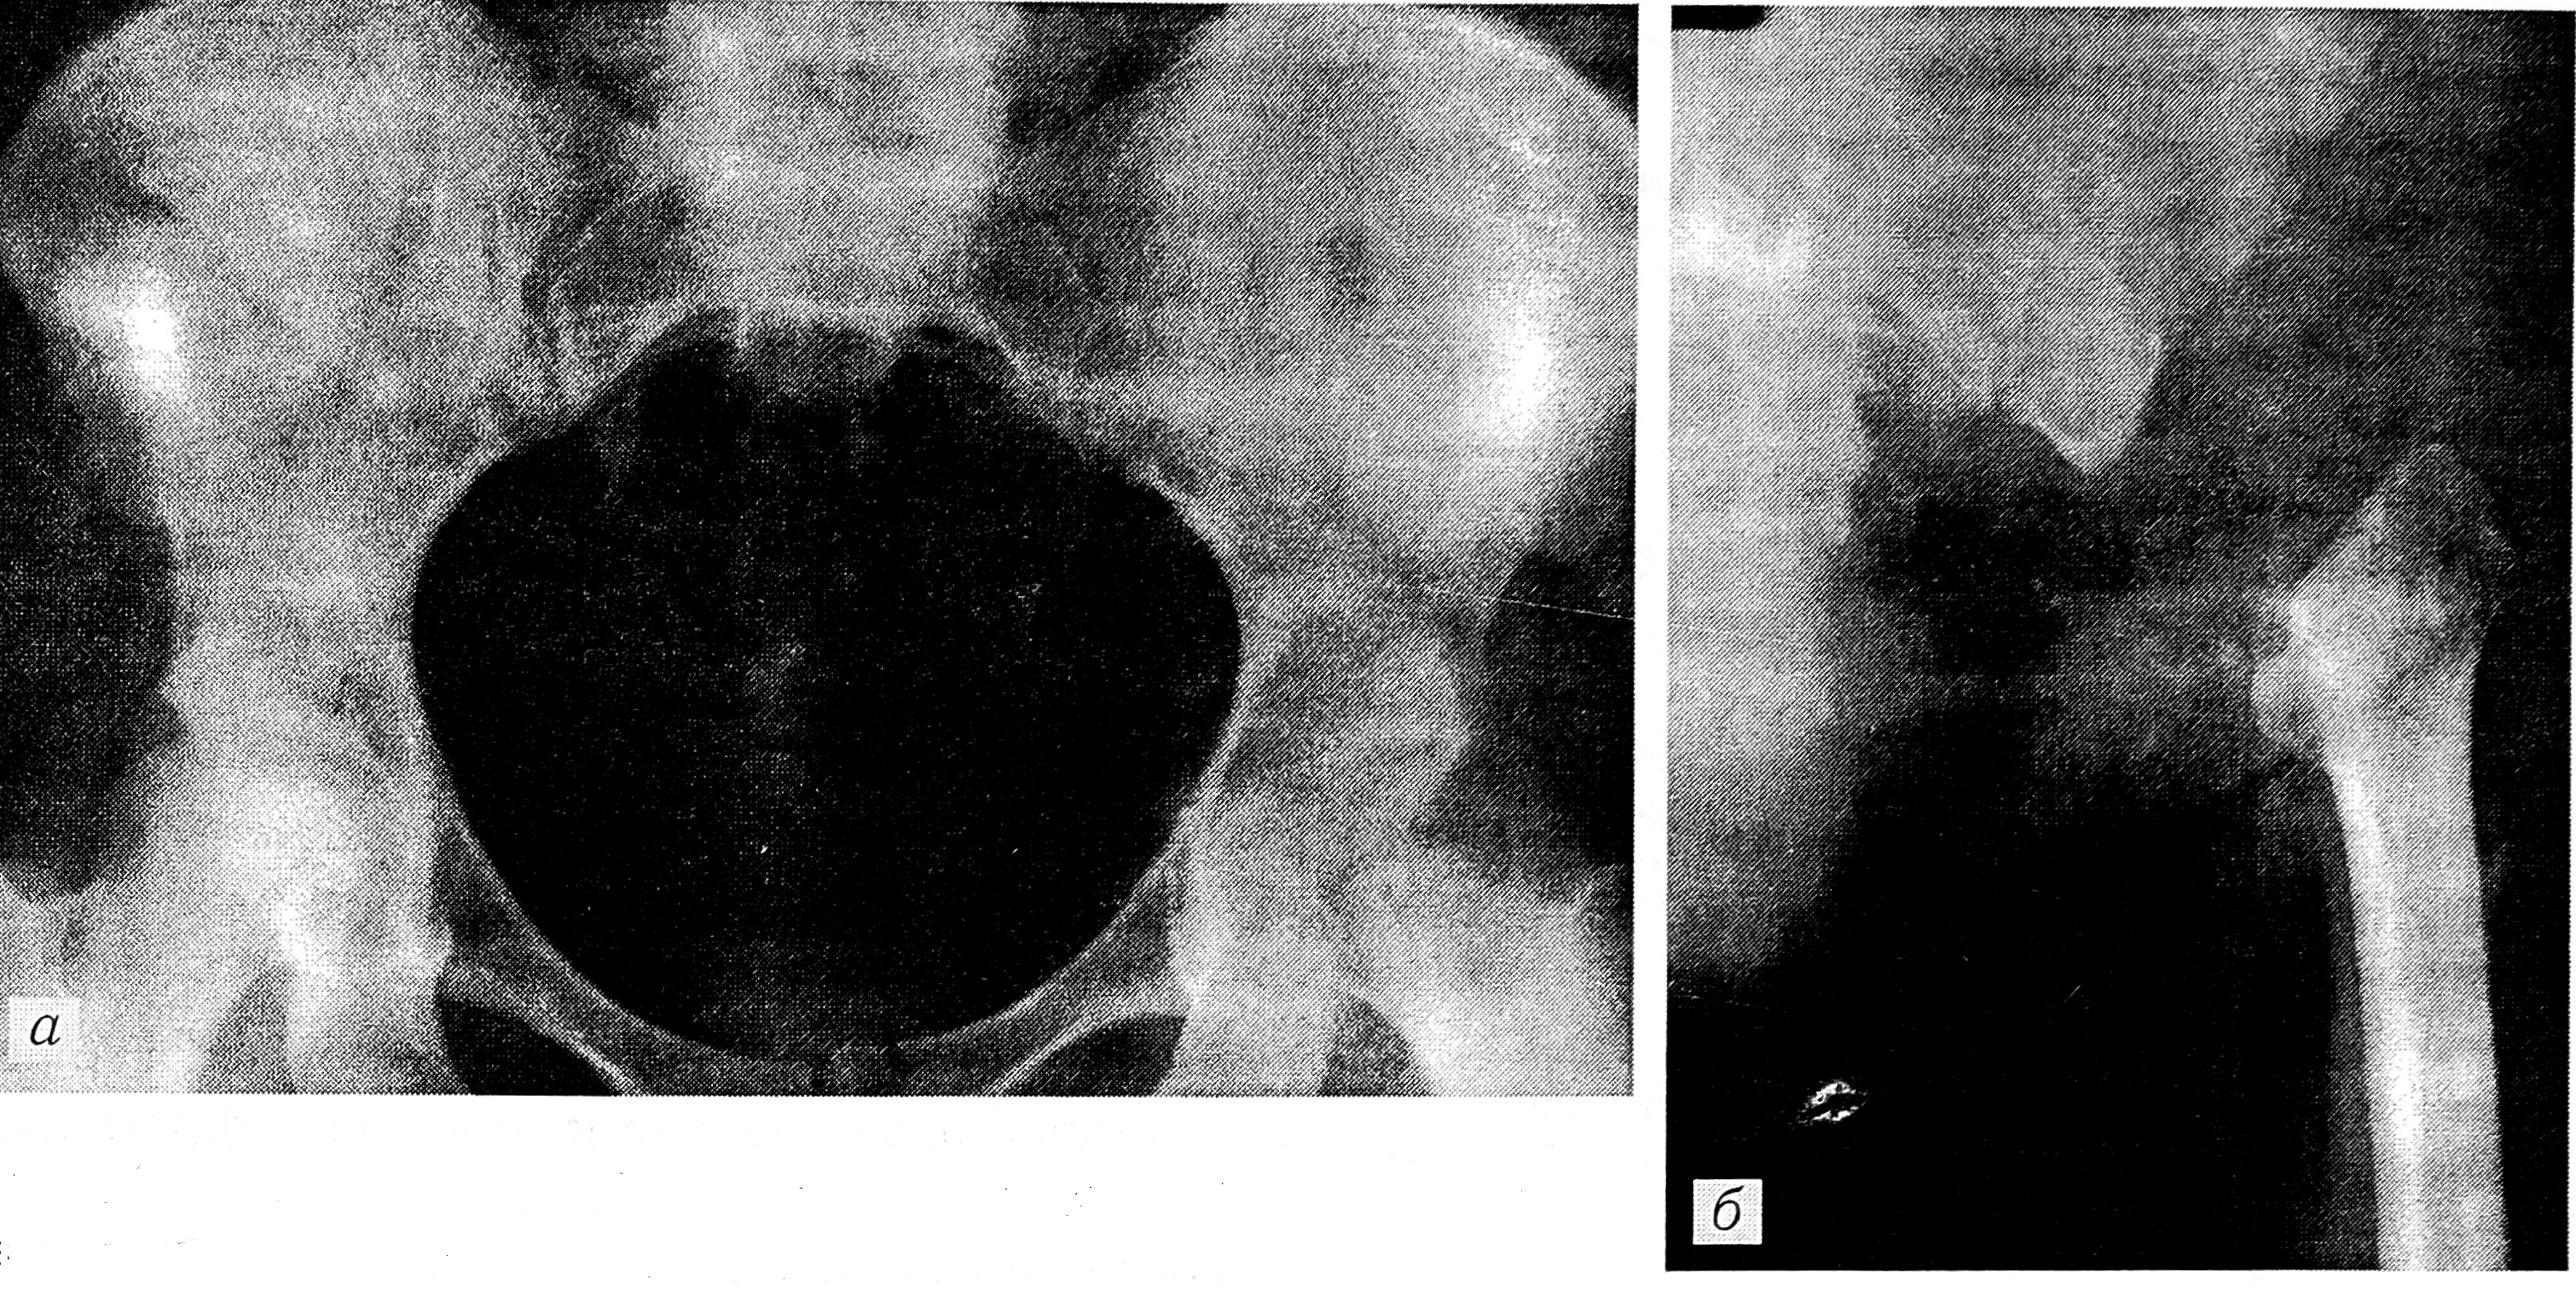

Больная С., 38 лет, до поступления в больницу № 62 в течение полутора лет подвергалась интенсивной физиотерапии, а затем противотуберкулезному лечению с предположительным диагнозом «коксартроз», а позднее — «туберкулез тазобедренного сустава». Диагноз хондросаркомы низкой степени зрелости тела подвздошной кости был поставлен после открытой биопсии. При обследовании в отделении: имеется обширный послеоперационный рубец в левой подвздошной области; пальпаторно опухолевое образование не определяется; движения в тазобедренном суставе ограничены и болезненны. Рентгенограммы легких: патологии нет. На рентгенограммах костей таза выявляется деструкция тела подвздошной кости слева, сужение щели левого тазобедренного сустава (см. рисунок, а).

Рентгенограммы больной С. до операции (а) и после межподвздошно-брюшной резекции (б).

18.06.90 больной произведена операция — меж- подвздошно-брюшная резекция. Опухоль удалена единым блоком, с лобковой, седалищной костями, телом подвздошной кости, головкой бедренной кости и подвздошно-поясничной мышцей. Целость опухоли нигде не была нарушена. Операция была произведена радикально и, с позиции оперировавшего хирурга (А.Н. Махсон), абластично. Через 1,5 мес после операции пациентка начала ходить с опорой на костыли. Через 1 мес после выписки появились боли в левой подвздошной области, интенсивность которых быстро нарастала. Больная была повторно госпитализирована. На рентгенограммах выявляется (нечетко) краевая деструкция крестца слева, состояние после межподвздошнобрюшной резекции (см. рисунок, б).